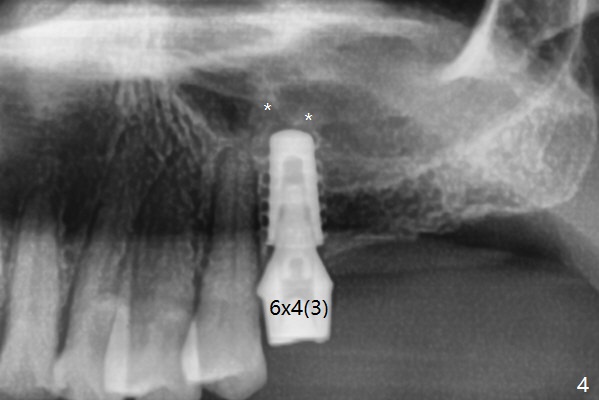

The long 4.8 mm Magic Drill (MD) is used as a tissue punch at the site of #14. After use of a curette to remove the tissue, the MD is used for osteotomy. In fact the osteotomy is mesial with an increase in the osteotomy depth. Magic Lifter, Magic Expander (3 mm) and Magic Drill (3.8 mm) are used to finish sinus lift. Following placement of PRF and Vanilla Graft, a 4.5x11 mm dummy implant is placed (Fig.1,2). The osteotomy seems to be mesial. After use of Lindamann bur distally and 2nd round of PRF membrane and Graft, a 5x9 mm implant is placed > 50 Ncm (Fig.3,4). The final implant appears to remain mesially radiographically. Retrospectively, 1.6 mm pilot drill should have been used with insertion of guide pin after tissue punch. Change in osteotomy position would have been much easier at the early stage. The patient returns for impression 3 months postop; There appears to be space mesial to the implant (Fig.5). The permanent crown will be cemented 2-3 months later. No screw loosens probably related to mesial placement of the implant.